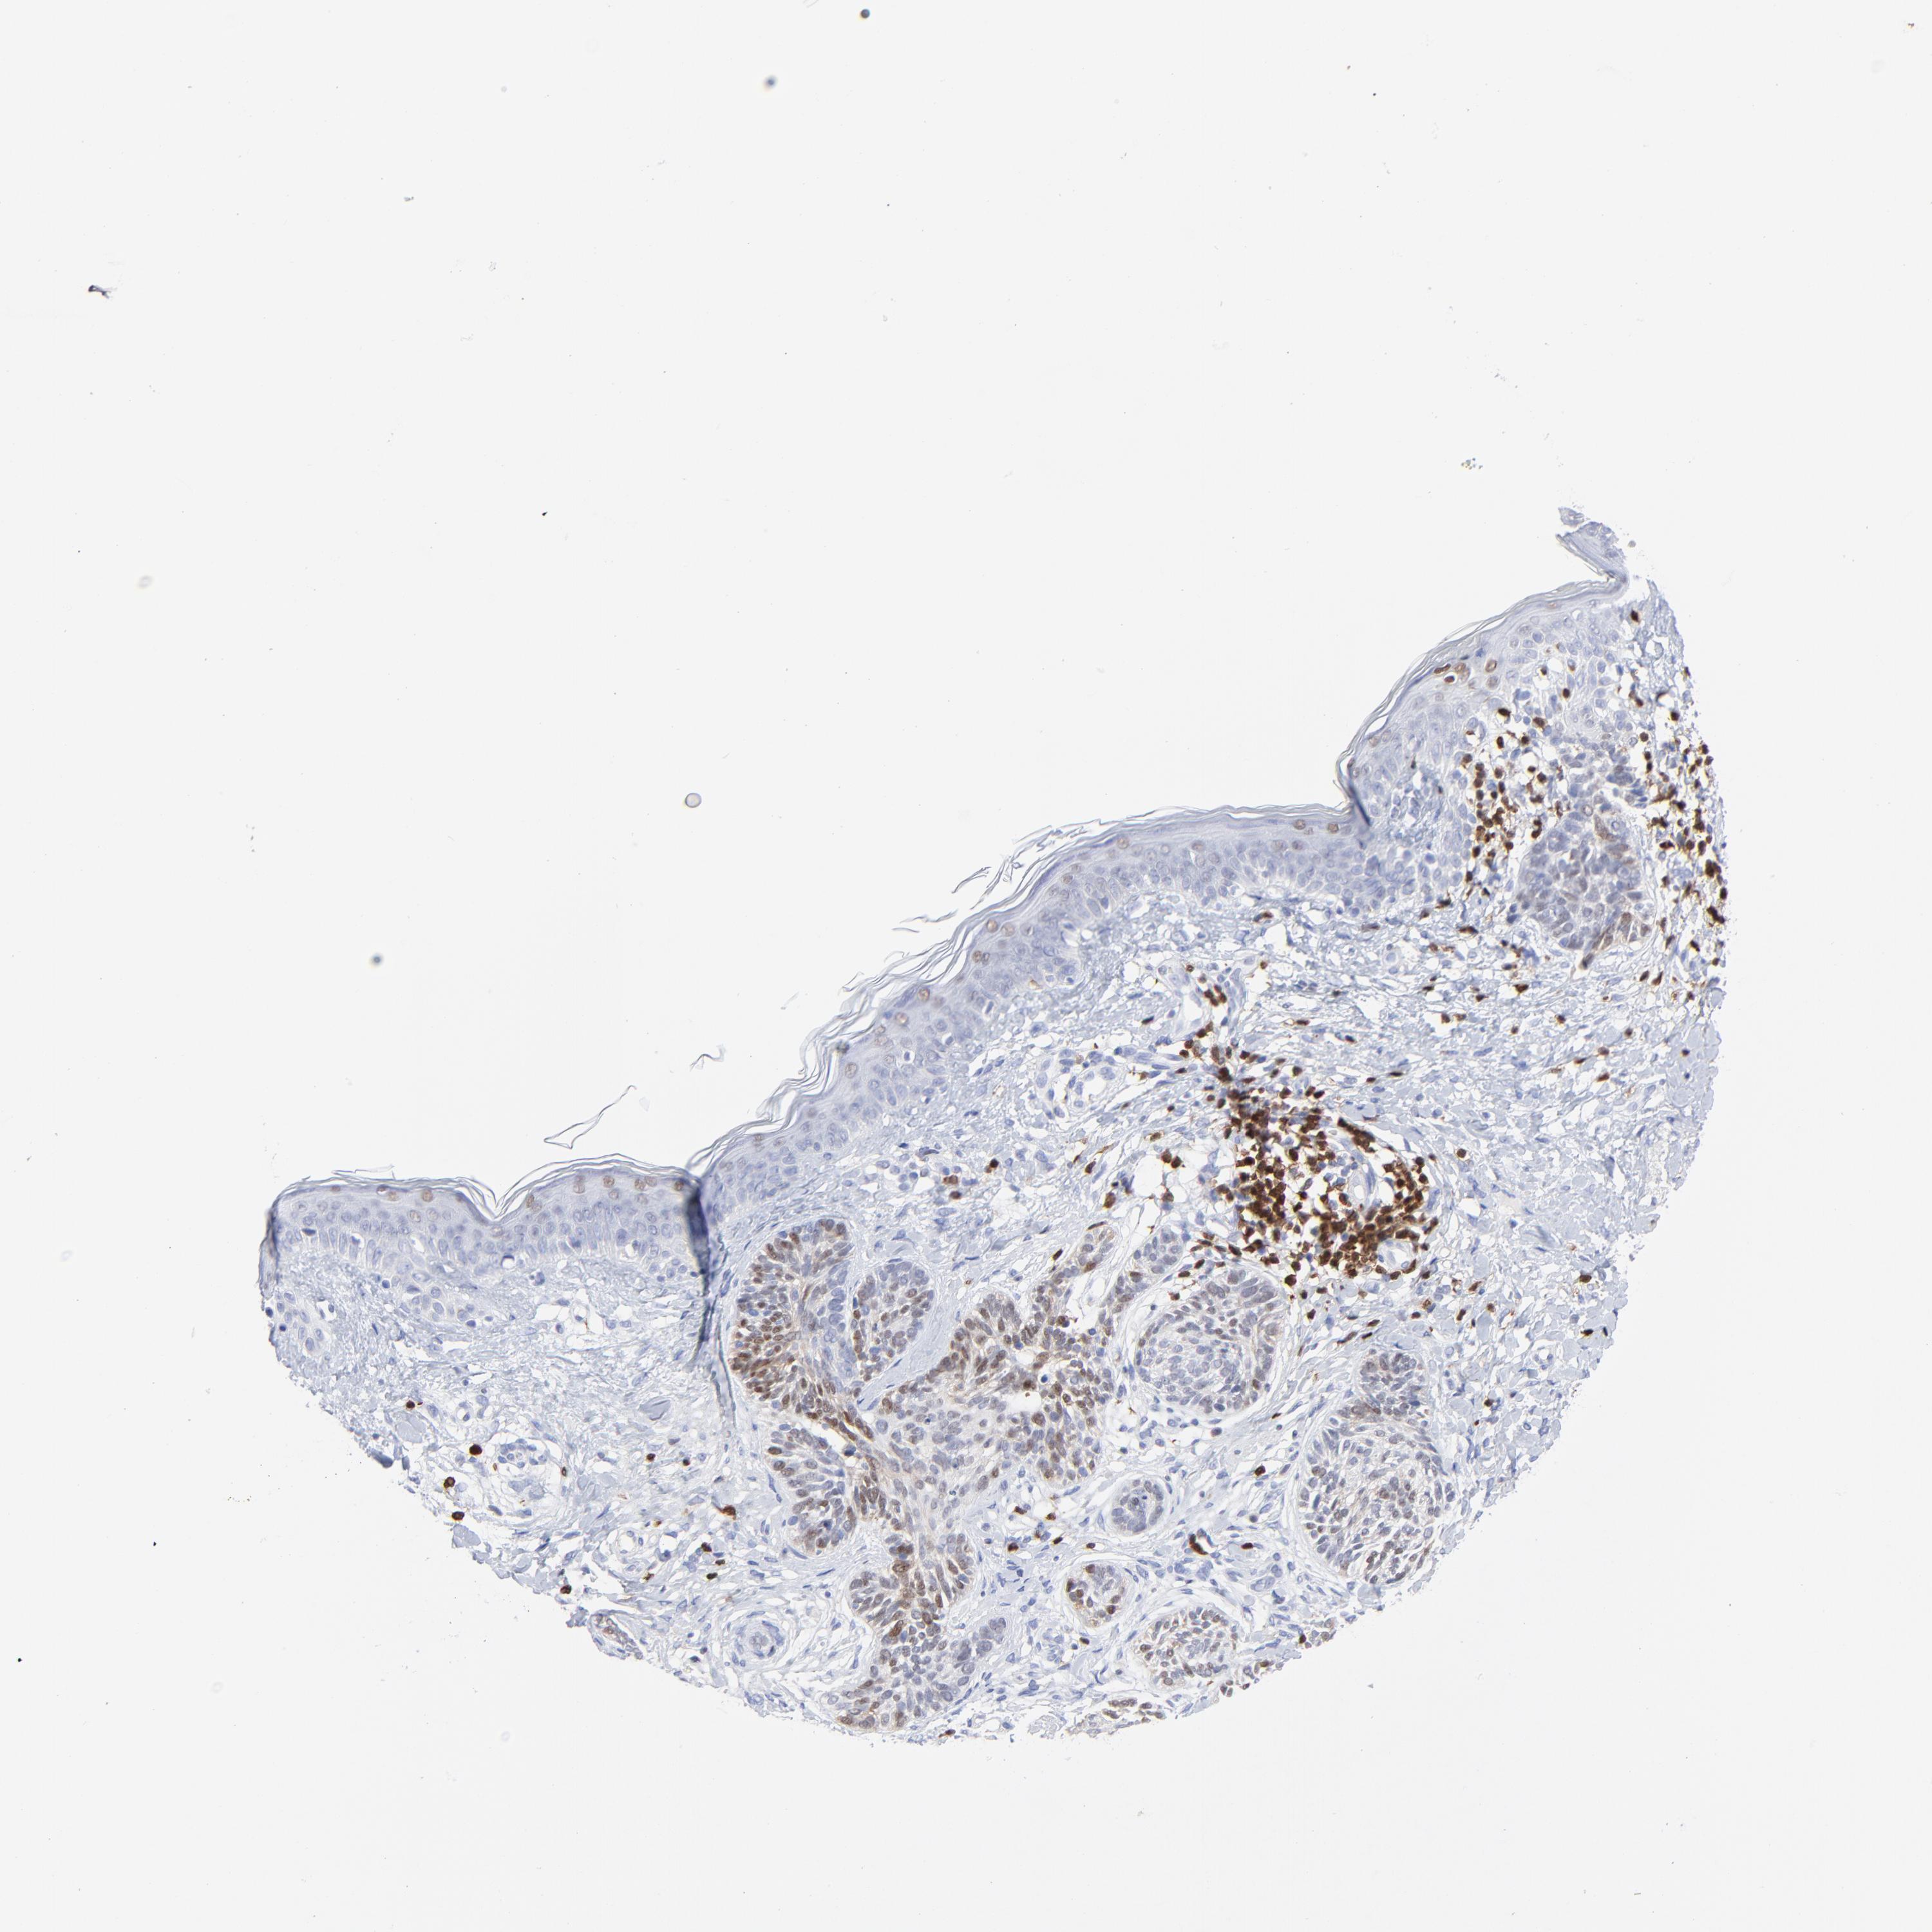

CANCER SKIN CANCER Show tissue menu

Basal cell and squamous cell cancer

SKIN CANCER - Protein expressioni

A mouse-over function shows sample information and annotation data. Click on an image to view it in a full screen mode. Samples can be filtered based on level of antibody staining by selecting one or several of the following categories: high, medium, low and not detected. The assay and annotation is described here.

Each image is clickable and will lead to virtual microscopy that enables deeper exploration of all samples and also displays staining intensity scores, fraction scores and subcellular localization as well as patient and tissue information for each sample.

Antibody HPA003134

Squamous cell carcinoma, NOS

Basal cell carcinoma